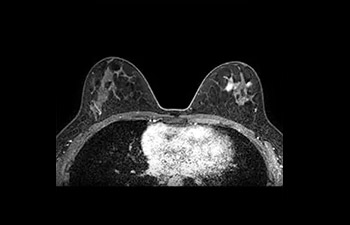

Beeldvorming van borst

met Compressed SENSE